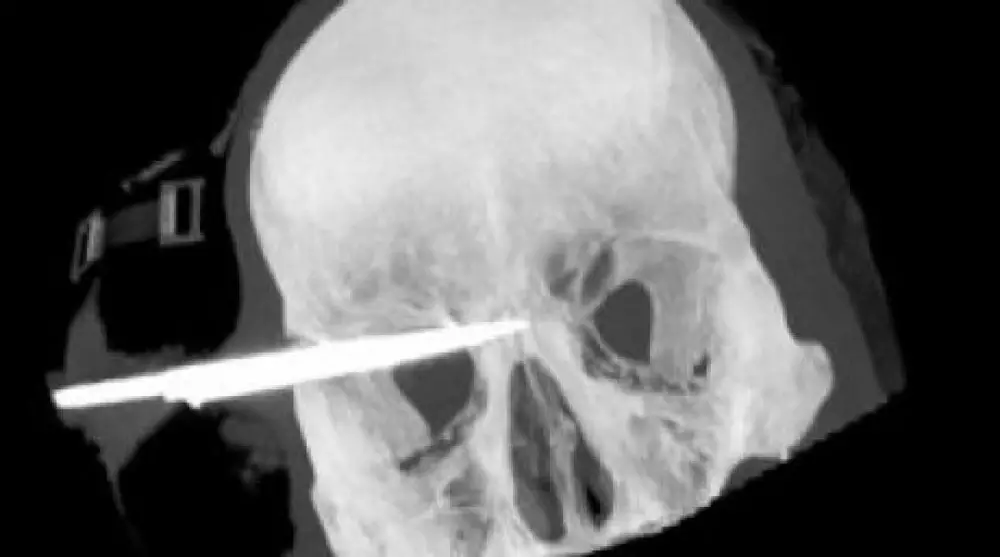

Житель Сальвадора прожил 18 лет с лезвием ножа в голове Предоперационный снимок. Фото с сайта tvnz.co.nz

Житель Сальвадора прожил 18 лет с лезвием ножа в голове, сообщает РИА Новости. Врачи одного из частных госпиталей Сальвадора извлекли девятисантиметровое лезвие ножа из головы человека, который жил с этим инородным предметом в черепе с 1995 года. Речь идет о сапожнике, подвергшемся нападению преступников-токсикоманов в начале 90-х. Они хотели отобрать у него сапожный клей, однако жертва оказалась не робкого десятка и вступила в драку с нападавшими. В результате сапожник получил ранение ножом в голову. Примечательно, что мужчина до 2007 года даже не знал, что часть лезвия осталась внутри черепа. И только когда его организм стал отторгать чужеродный предмет, и у него сильно заболела голова, он прошел дополнительное обследование. Операция по извлечению ножа длилась 7 часов и потребовала участия бригады нейрохирургов. В настоящее время пациент уже пришел в себя, говорит и находится в сознании, сообщили медики. Врачи раскритиковали своих коллег, которые в 1995 году оказали помощь пострадавшему, но при этом не сообщили пациенту, что в его голове осталась часть лезвия.